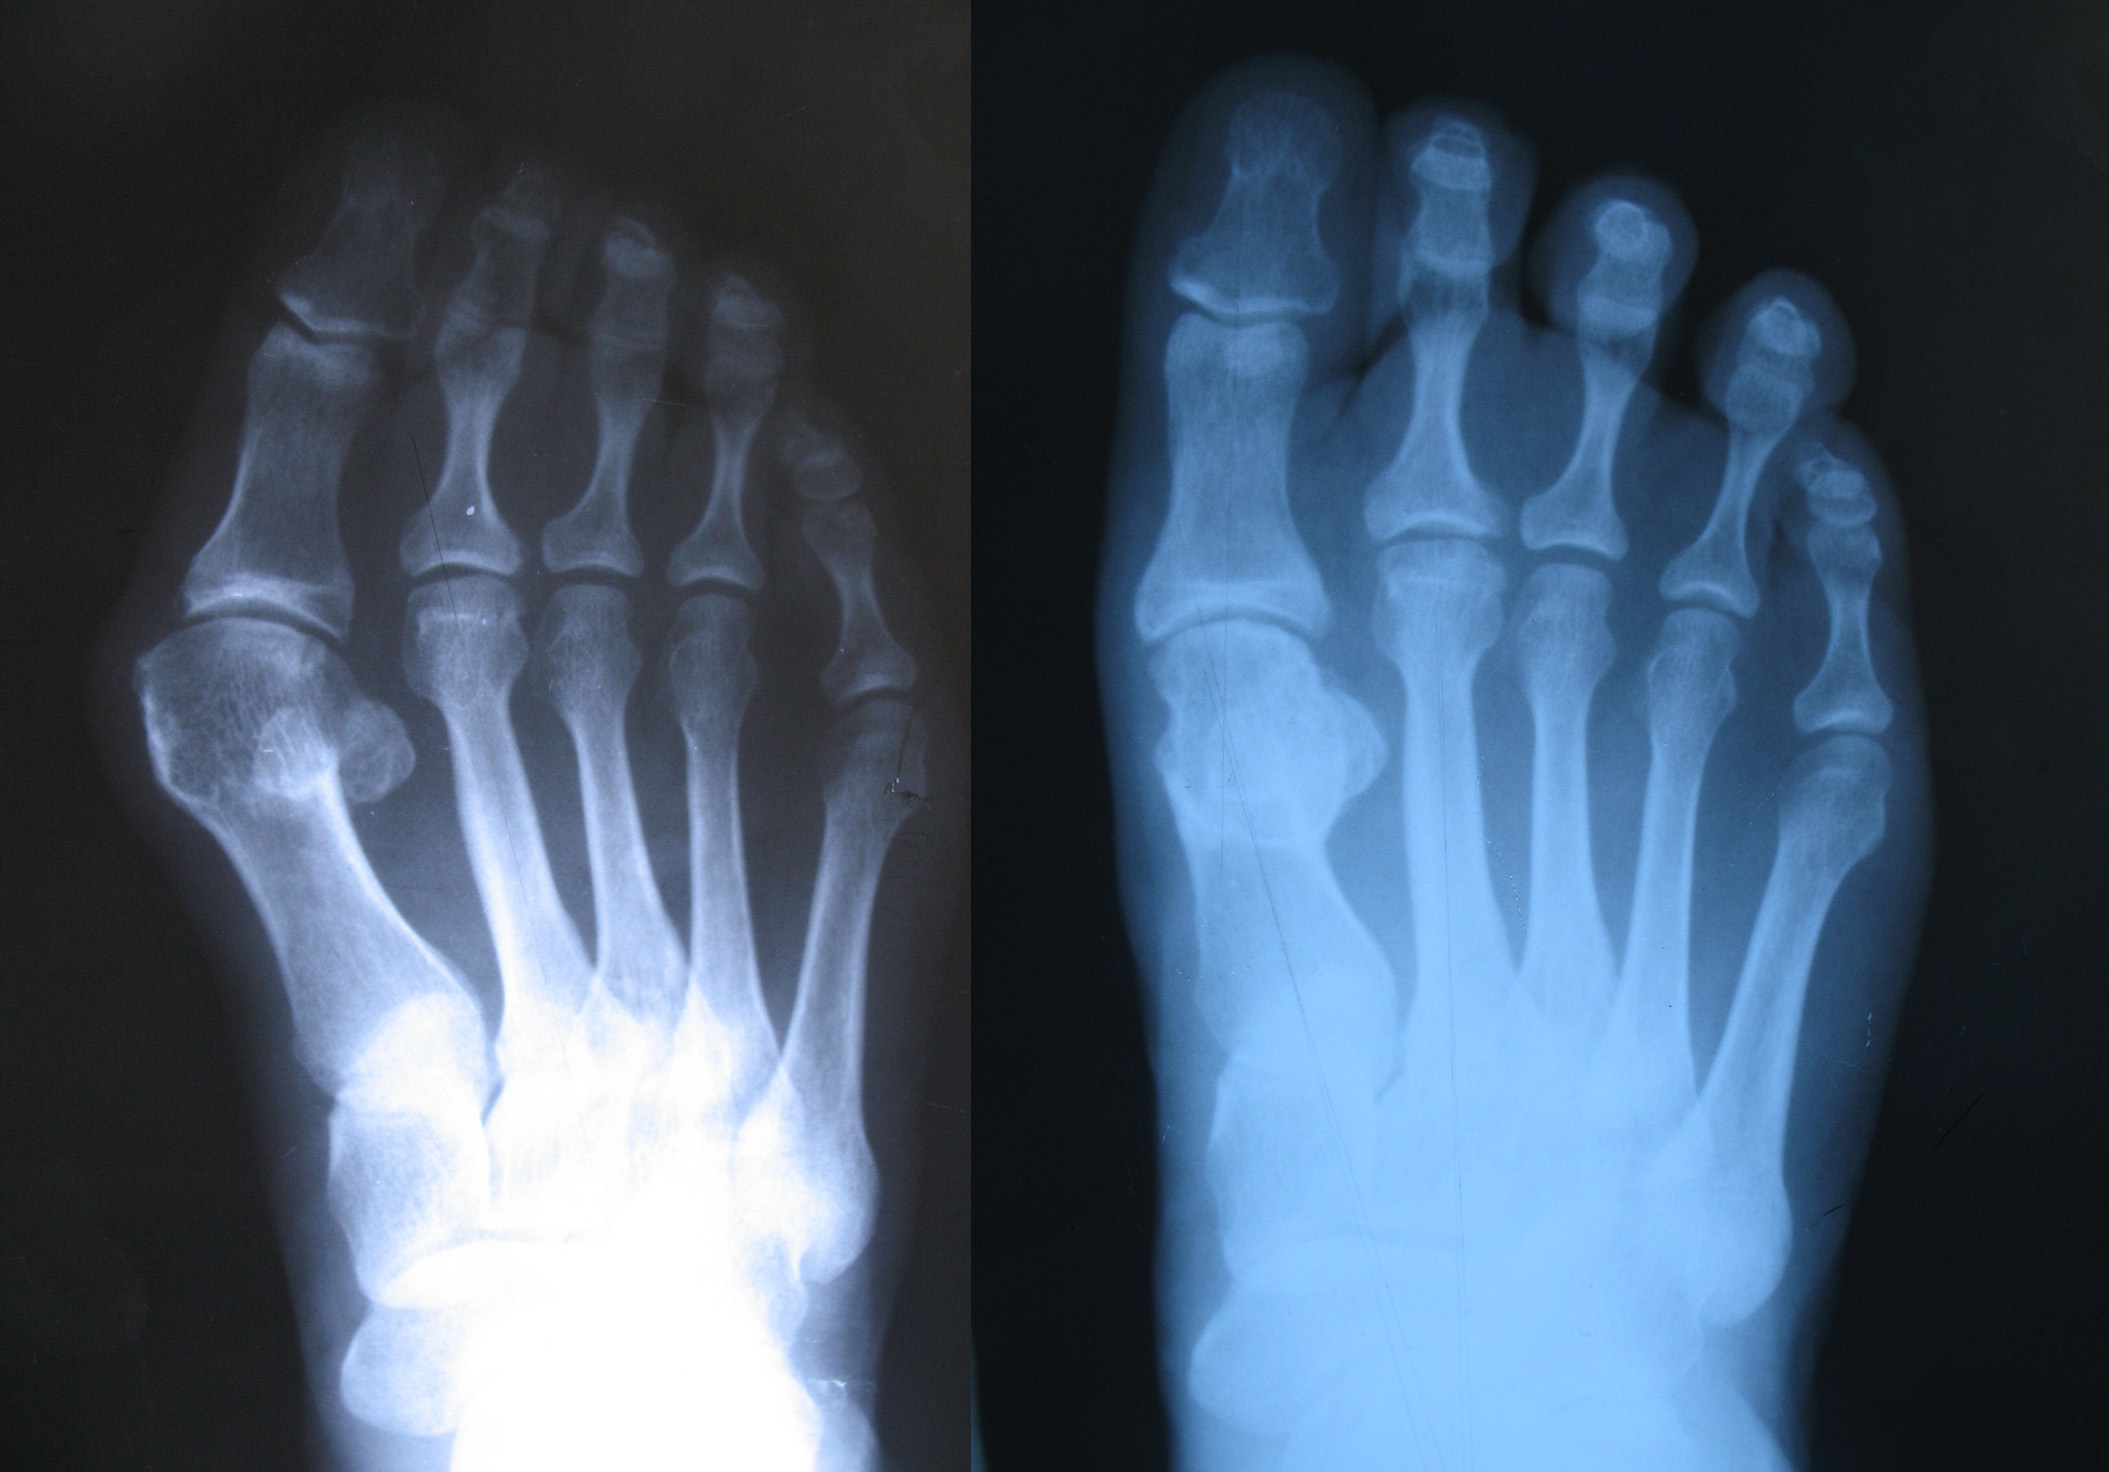

手术前后X线对比